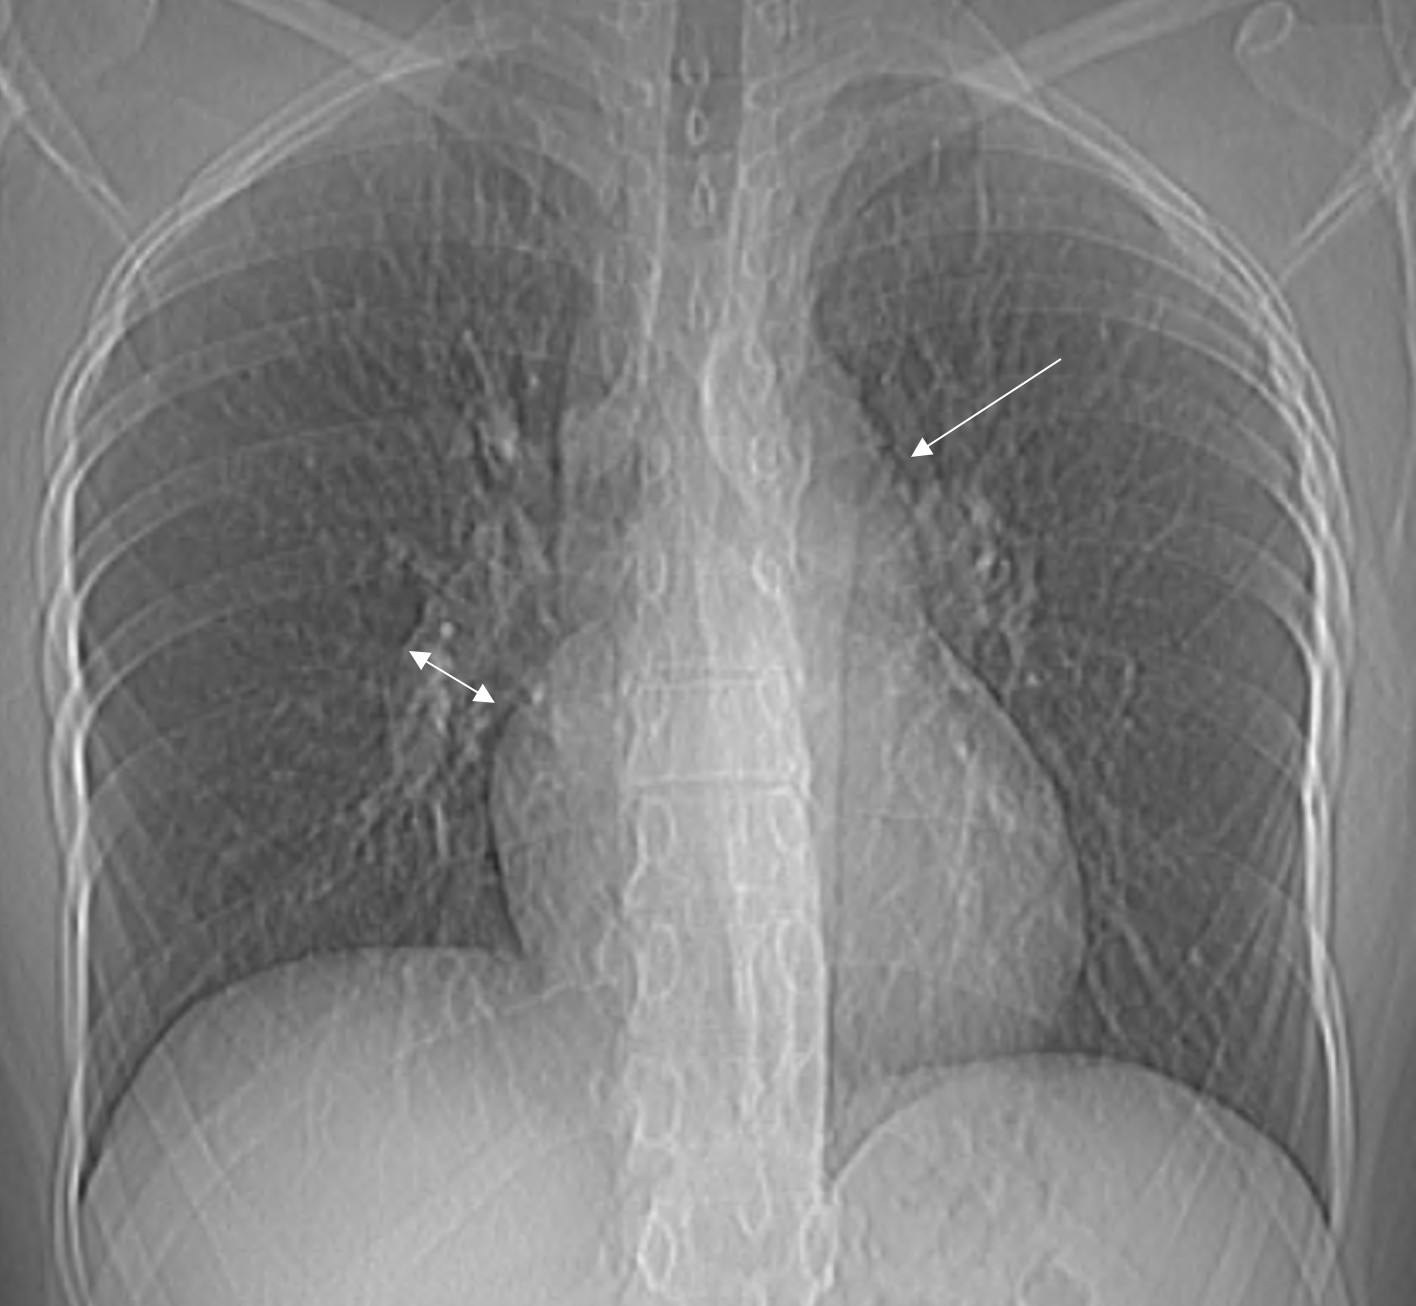

1. Рис.1 Рентгенограмма лёгких, прямая проекция. | |

5. Рис.5 Рентгенограмма лёгких, прямая проекция. | |